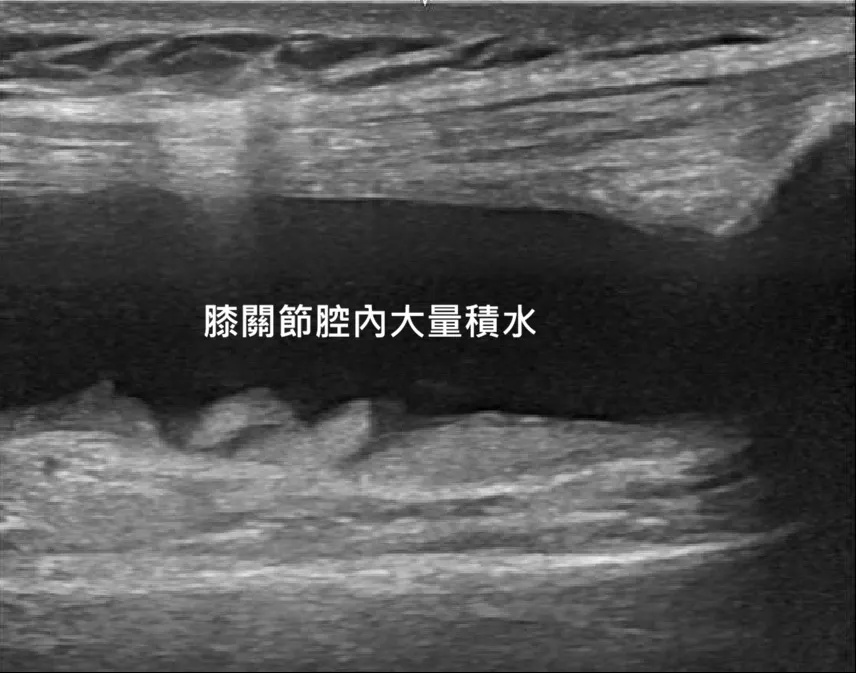

🔍 超音波下的真相:X 光看不到的秘密

很多患者會問:「醫師,我 X 光照出來骨頭還好,為什麼膝蓋這麼腫、這麼痛?」其實,X 光只能看硬骨頭,軟組織的問題(積水、半月板、發炎)必須靠高解析超音波才看得到。在宸新復健科的檢查螢幕上,我們會帶您看到以下狀況:

1. 膝關節積水 (Joint Effusion)

正常的關節液只有一點點。但在超音波下,若看到髕骨上方出現「黑色的不規則區域」(黑色代表液體),那就是積水。這代表關節內正處於急性發炎狀態,會讓膝蓋非常腫脹,抽出後會舒服很多,施打PRP或玻尿酸前也一定要抽出,以免跟積水混在一起影響效果。